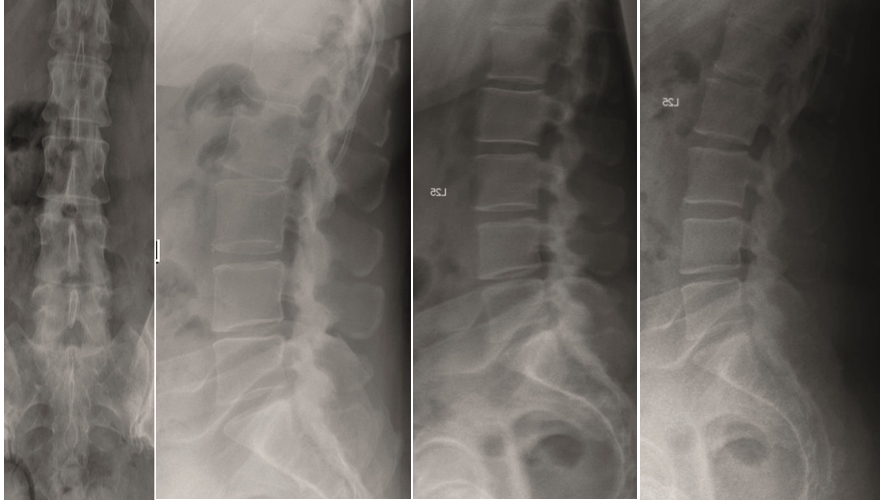

A female patient 66-years-old with back pain, leg pain, and degenerative deformity. The x-rays show left convex degenerative scoliosis Cobb T12-L3 38. Nonoperative treatment failed. Treatment option was posterior fusion T11-L5, with URS Facet Wedge L2-L3 unilaterally.

A conventional approach for posterior correction was taken, with indirect Foraminal decompression and Facet Wedge fusion (apex curve). Facet Wedge introduction after curve correction with rod in situ. X-ray follow-up initially (Fig 20), with CT assessment of Facet Wedge fusion after 6 months (Fig 21).